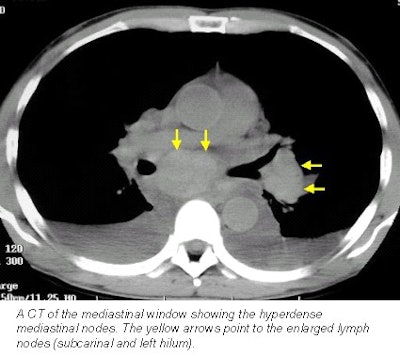

Cerva observed a profuse and slightly hyper-attenuating paratracheal, anteroposterior (AP) window, subcarinal, hilar, and azygo-esophageal recess lymphadenopathy. In addition there was diffuse mediastinal edema, bilateral pleural effusions, bibasilar airspace disease, more pronounced on the left, and thickened peribronchial tissue (seen best on lung windows).

A noncontrast CT scan was performed on the patient using the institution’s standard chest protocol. Berman found a profuse and slightly hyper-attenuating paratracheal, AP window, subcarinal, hilar, and azygo-esophageal recess lymphadenopathy similar to what Cerva had observed a few hours earlier in the first patient.

She also saw diffuse mediastinal edema, bilateral pleural effusions, and thickened peribronchial tissue. In this patient, however, bibasilar airspace disease was more pronounced on the right.

Earls and his fellow radiologists believe the presence of enlarged hyperdense nodes depicted on the noncontrast CT, in the clinical setting of exposure to an anthrax "hot spot," along with concurrent flu-like symptoms, should be considered a positive screen for active inhalation anthrax.